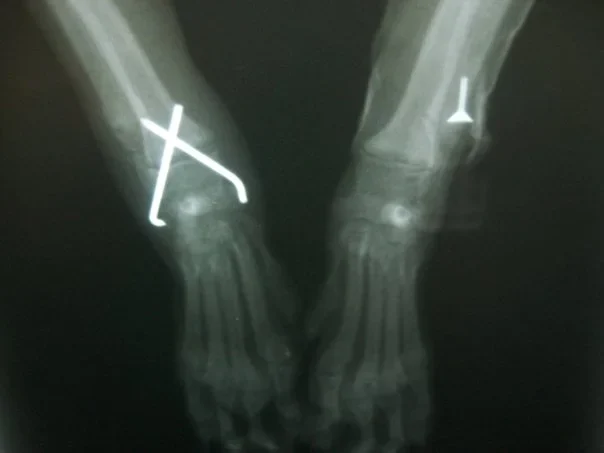

Galería de casos clínicos

Casos clínicos de cirugía (tejidos blandos, traumatología, neurocirugía, artroscopia)